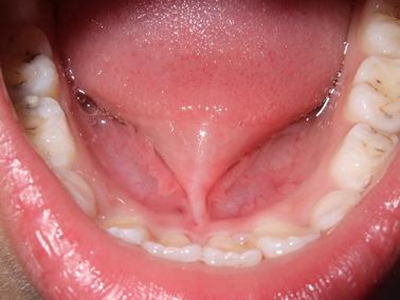

舌系带过短是指孩子出生后舌系带没有退缩到舌根下,出现舌系带形态或附着位置异常,导致的舌头不能伸出口外,舌尖不能上翘。可不同程度地影响唇、舌的运动,发生哺乳、咀嚼、发音等功能障碍,常需作矫正手术。

舌系带过短多见于儿童,张口时,舌体挛缩,可暴露舌系带。伸舌时,舌不能自然伸至下唇外侧,用力伸舌时舌尖呈“V”字形或“W”型凹陷。语言障碍患者不能发出舌腭音及卷舌音,发音吐字不清。舌系带过短的幼儿哺乳时,由于舌前伸时系带与下前牙切端摩擦,易形成溃疡、疼痛,导致哺乳障碍。